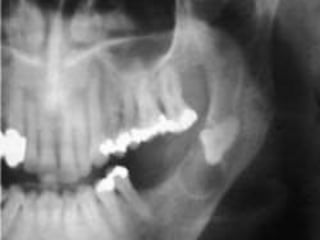

Case

 18 year-old female with several month history of lesion

in right maxilla, treated initially by oral surgeon with

multiple curettage.

 Has experienced recent onset of rapid expansion, with

complaints of loose dentition and pain.

Case  18 year-oldfemale with several month history of lesion in right maxilla, treated initially by oral surgeon with multiple curettage.  Has experienced recent onset of rapid expansion, with complaints of loose dentition and pain.